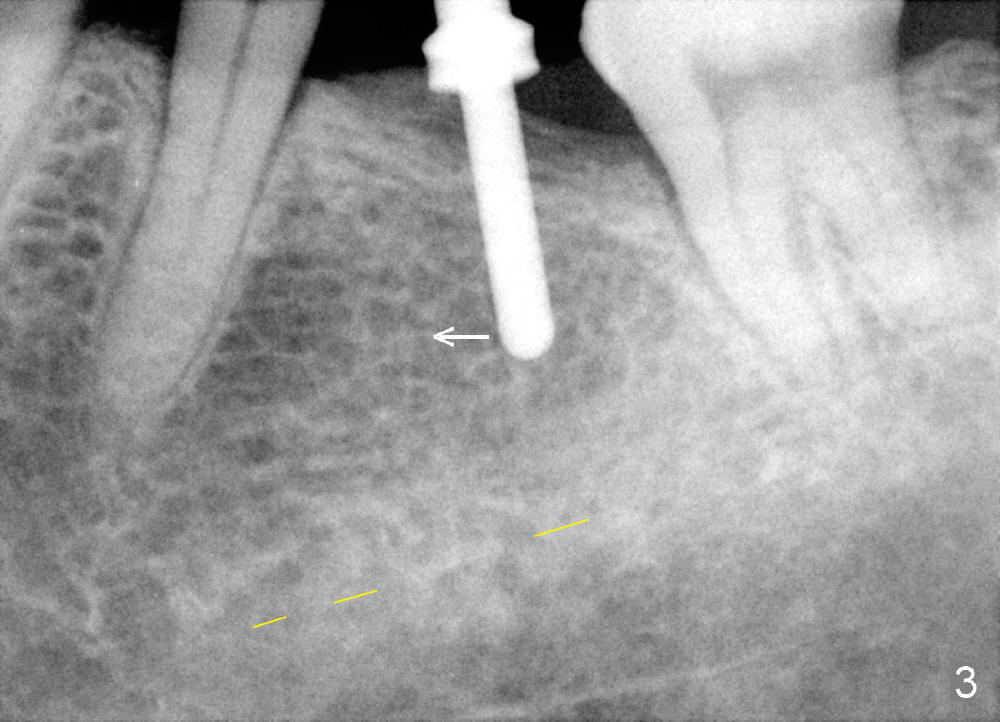

A 65-year-old man has a failing fixed prosthesis replacing the tooth #19 (Fig.1). The distal abutment tilts mesially (red line) with evidence of occlusal trauma (>). The implant at the site of #19 is intentionally placed distally (black outline) and will be used as an anchorage once osteointegrated to upright #18. Ultimately the mesiodistal width of #19 crown will be ideal.